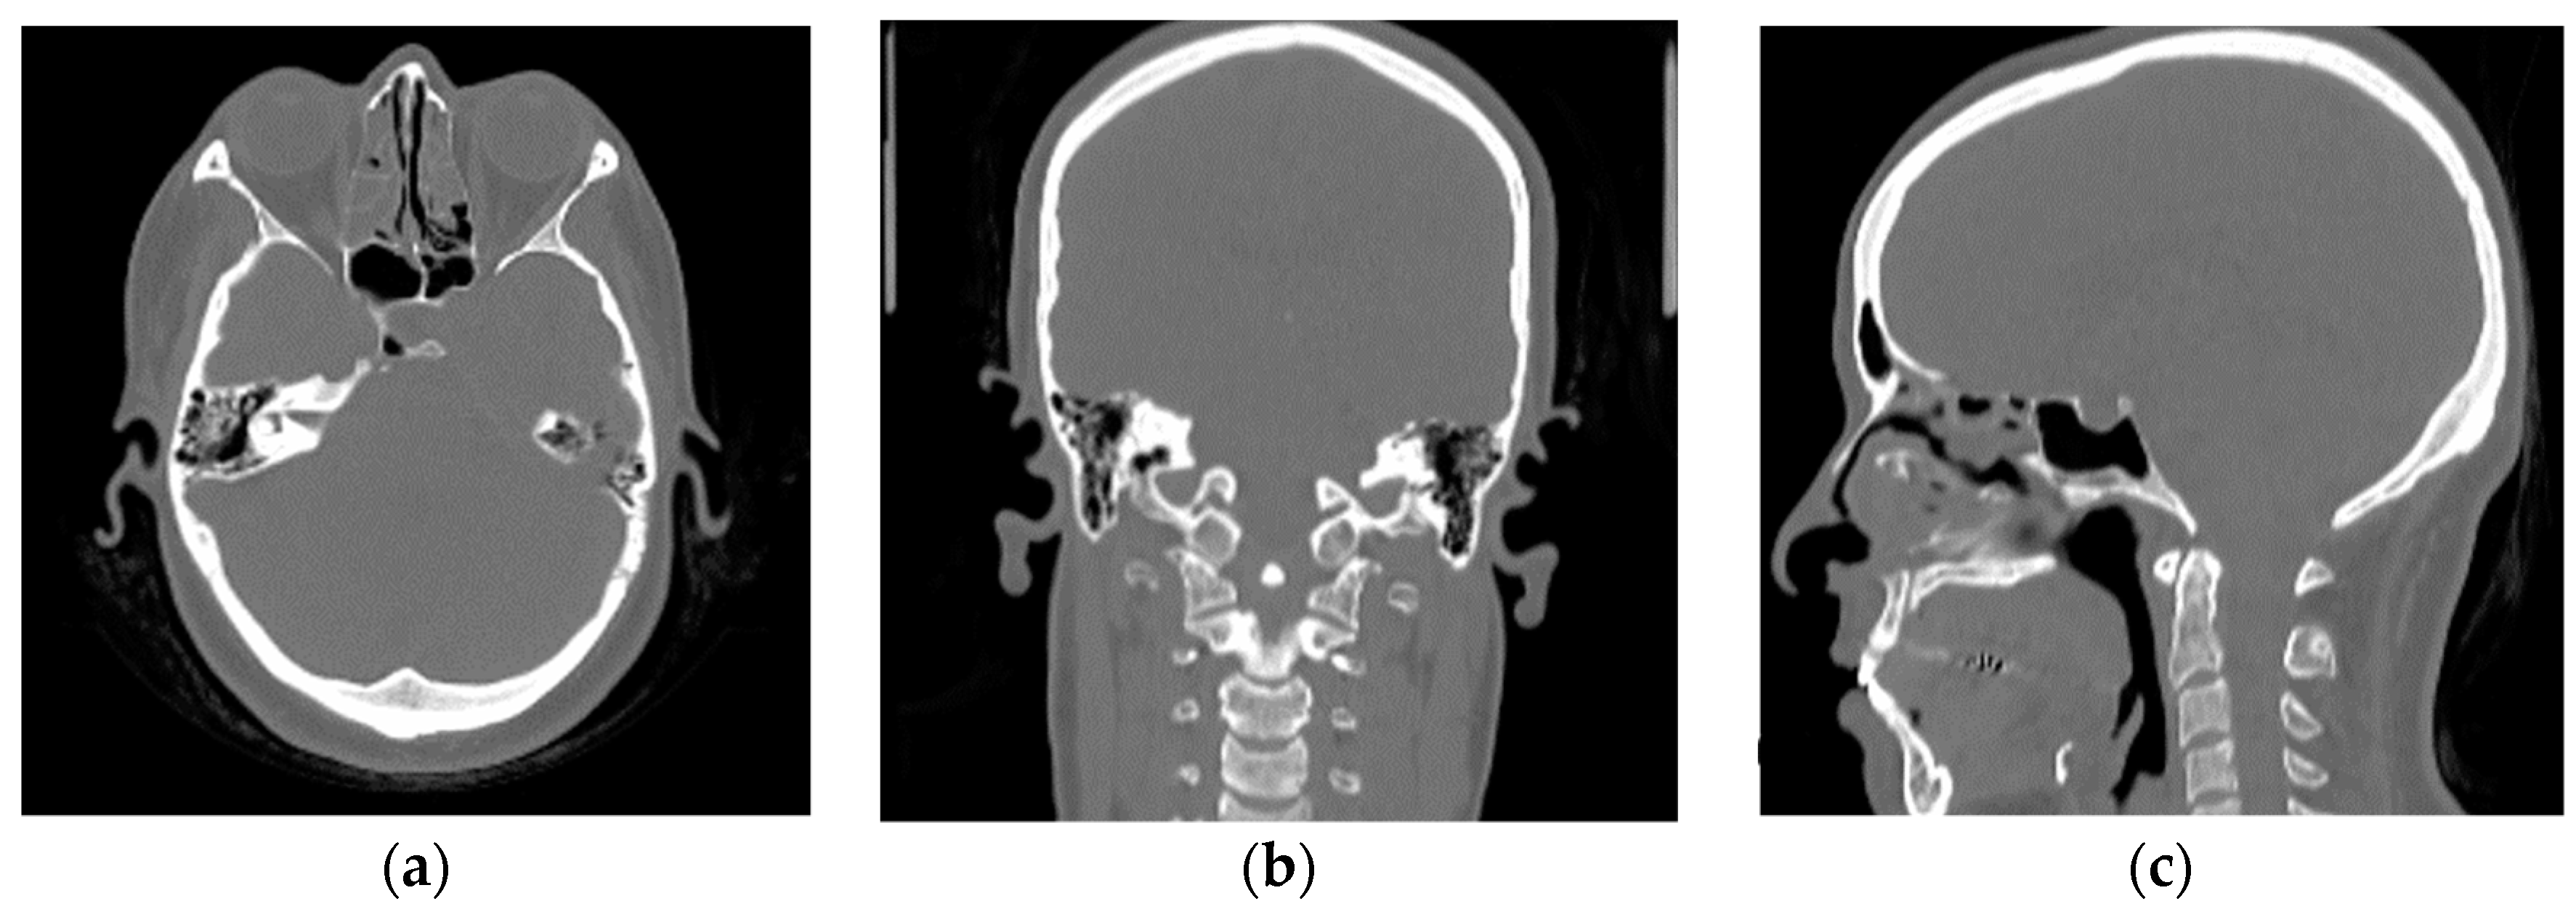

2.2.2. Validation Dataset